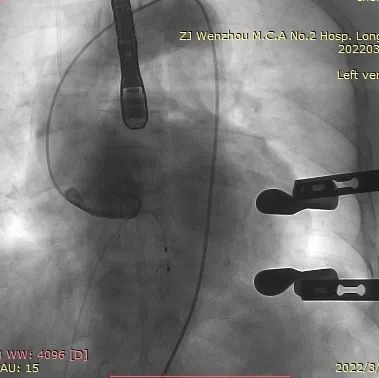

术中影像监护与评估(DSA&TEE)

瓣膜释放泥鳅导丝和单弯管过弓

加硬导丝建立轨道

介入器过瓣环平面

释放定位件

瓣膜入座

瓣膜自膨

松开锁丝,撤出输送器

DSA和TEE显示无瓣周漏,瓣膜位置、形态良好